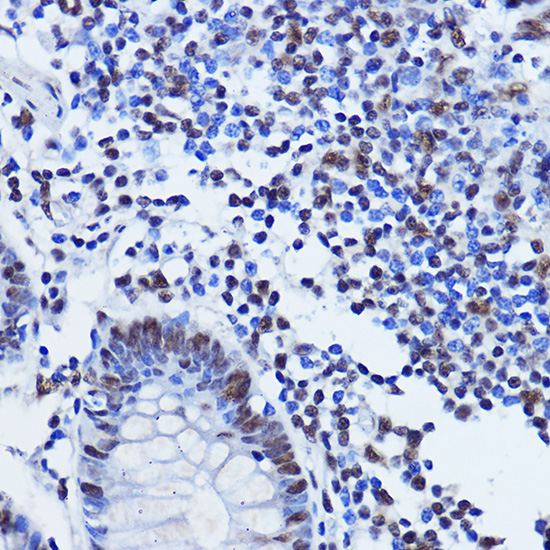

Immunohistochemistry of paraffin-embedded human colon using TDP-43/TARDB Rabbit pAb.

,